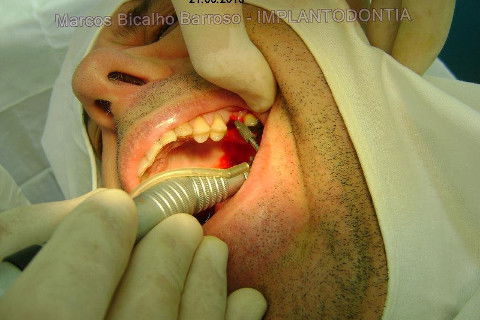

Implante Alvim Cone Morse - Instalação em 20 Minutos, Sem Retalho, Sem Sutura

Instalação de um implante em região do 26. Utilizamos um implante cone morse Alvim Neodent 4.3 X 11,5. Foi uma cirurgia muito rápída e minimamente traumática, sem retalho e sutura.